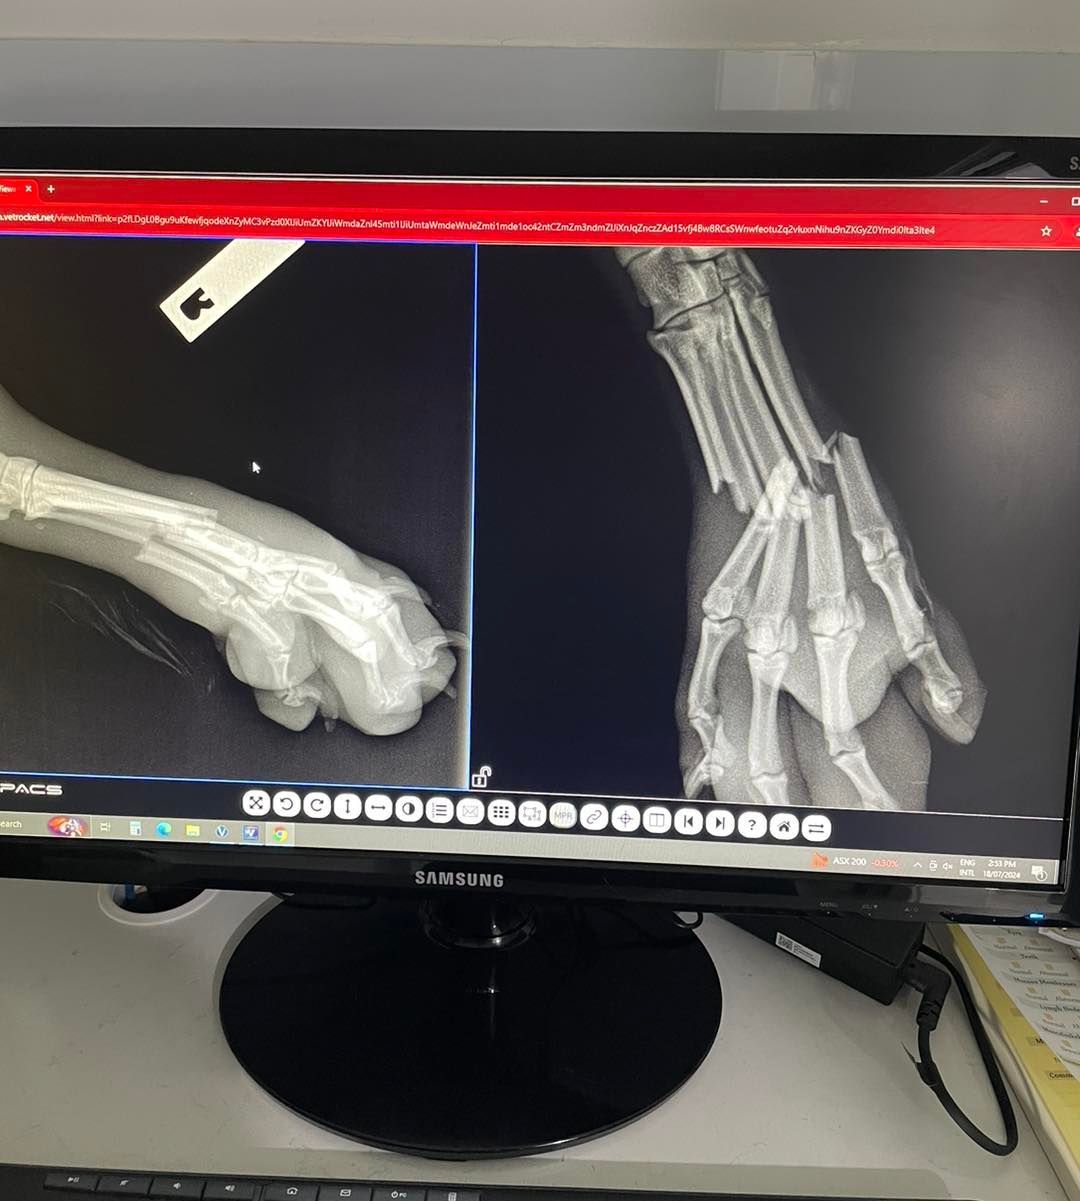

X-Rays

One of the most common diagnostic tools we use in veterinary clinics is radiographs (or X-rays). Cowra Veterinary Centre is fully equipped to take and immediately process radiographs of your pet. Radiographs are particularly useful for diagnosing problems in animal bones, the chest (heart/lungs) and abdomen. After our veterinarians have discussed your pet’s condition and fully examined your pet, they will advise you whether radiographs are required.

A radiograph is very similar to a photo, except that X-rays instead of light rays are used to capture the image. X-rays penetrate dense tissue (such as bone) less than they penetrate soft tissue (such as lungs). So these different tissues show up as different shades of white/grey/black on a radiograph. Bone absorbs the most X-rays, so it shows up as white on a radiograph, while soft tissue (such as liver or intestines) will appear as shades of grey. Air shows up as black on a radiograph, so lungs should appear black, assuming they are full of air. We will show you your pet’s radiographs and explain our findings when your pet goes home.

Most of our patients are admitted into hospital for the day to have radiographs taken, except for emergencies, where we will admit them immediately. Please bring your pet in without being fed on the morning of their appointment, as they may need to be sedated or anaesthetised to allow us to take the best quality radiographs possible. After the radiographs have been taken and your pet is ready to go home, one of our veterinarians will show you the radiographs and discuss our findings and treatment plan.

Will my pet need to be sedated or anaesthetised to have radiographs taken?

To get an accurate diagnosis of your pet’s condition, we need high-quality radiographs. To get these radiographs, it may be necessary to give your pet sedation or anaesthesia, as most pets will (understandably) not lie still enough in the correct position while we take the radiograph. This is especially true if your pet’s condition is painful (e.g., fractures).Sedation and anaesthesia also mean we can minimise the number of radiographs we have to take, which is safer for your pet and for our veterinary staff.